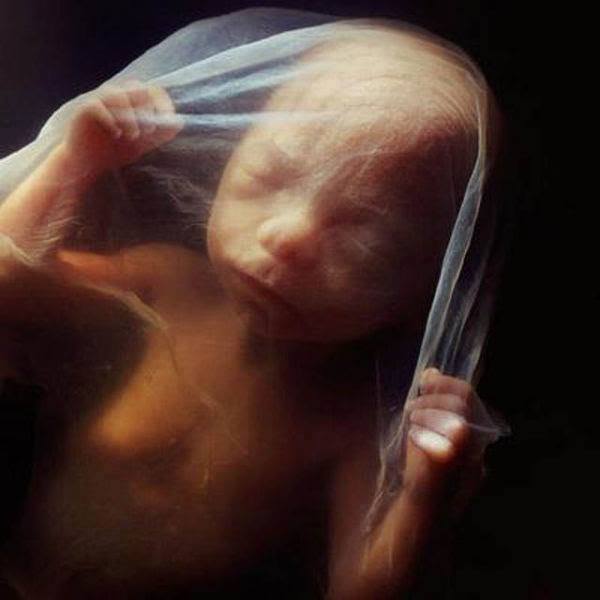

| 16 weeks.The foetus uses its hands to explore its own body and its surroundings |

| The skeleton consists mainly of flexible cartilage.A network of blood vessels is visible through the thin skin |